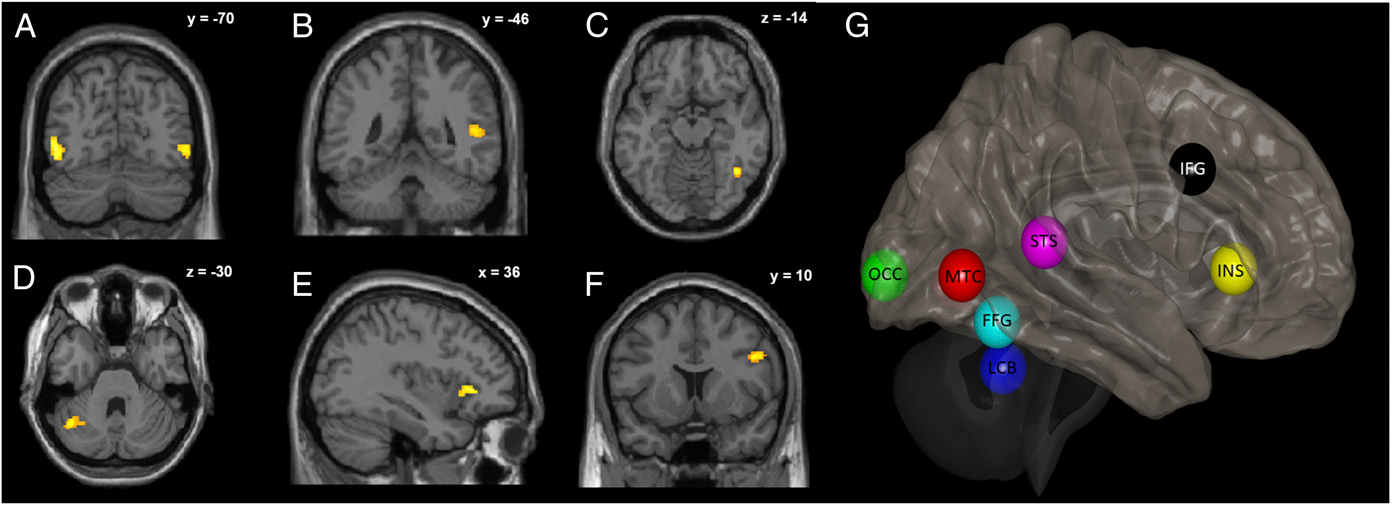

Das Gehirnnetzwerk, das der visuellen Wahrnehmung getarnter Körperbewegung zugrunde liegt (A - F). Regionen mit erhöhter fMRT-Aktivierung während der Wahrnehmung von Körperbewegung liegen im bilateralen medialen Schläfenlappen (A), rechten oberen temporalen Sulcus STS (B), rechten Gyrus fusiformis (C), linken lateralen Kleinhirn‑Läppchen Crus I (LCB) (D), in der rechten vorderen Insula INS (E) sowie dem rechten unteren frontalen Gyrus IFG (F). (G) Übersicht über die 7 Netzwerkknoten (einschl. der visuellen Großhirnrinde, OCC), die bei der Erkennung getarnter Körperbewegung zusammenspielen. Diese Regionen wurden bei der probabilistischen Traktografie und dem sog. Dynamischen Kausalen Modellieren (DCM) verwendet. Aus Sokolov et al. (2018). Proc Natl Acad Sci U S A. 115(51):E12034-42.

Die visuelle Wahrnehmung von Körperbewegungen ist für soziale Kognition und unseren Alltag von großer Bedeutung. Ein innovativer und integrativer Ansatz bei der Analyse der Gehirnkonnektivität beleuchtet nun den Aufbau und die Funktionsprinzipien des zugrundeliegenden Großhirn-Kleinhirn‑Netzwerks: Anstelle einer hierarchischen Organisation zeigt sich das Netzwerk eher parallel aufgebaut. Dies könnte erklären, warum bei fokalen Hirnschäden das Lesen von Körpersprache weitgehend intakt bleibt, während es bei neuropsychiatrischen Erkrankungen mit verteilten Netzwerkstörungen oft stark betroffen ist. Zudem lässt sich visuelle Sensitivität gegenüber Körperbewegung durch ein spezifisches Top-Down-Feedback zur visuellen Großhirnrinde sowie durch funktionelle Kommunikation (sog. effektive Konnektivität) und das Vorhandensein von Fasern der weißen Substanz zwischen dem fusiformen Gyrus und Sulcus temporalis (einem Schlüsselzentrum des sozialen Gehirns) am besten vorhersagen. Die Ergebnisse fördern damit ein besseres Verständnis des sozialen Gehirns.